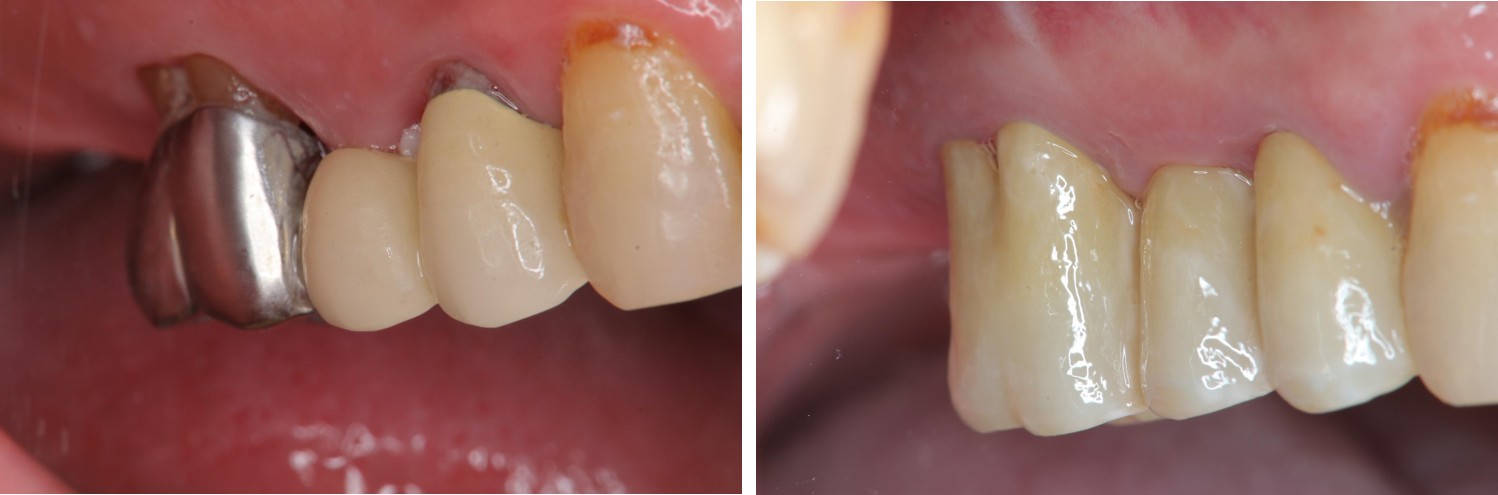

術前、術後比較

治療後,牙周咬合良好

治療後,密合度良好